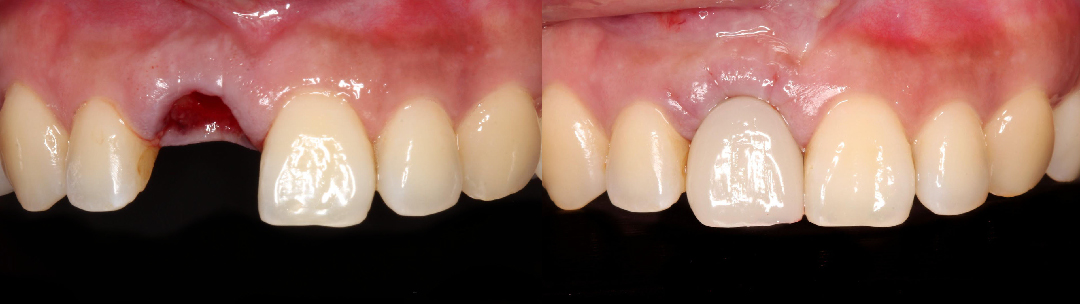

照片經當事人同意由當代牙醫植牙中心公開使用,實際效果因個人條件不同有所差異。

最讓我開心的是,手術當天就有臨時假牙,不用擔心沒有門面,而且最後還可以自己挑選假牙的顏色,做出來的外型非常自然,家人和同事都看不出來是假牙,真的很滿意!

手術植入人工牙根,立即裝上臨時固定假牙,快速恢復美觀、減少缺牙空窗期。

植牙前缺牙影響美觀與咀嚼功能,植牙後恢復完整牙列,不僅提升自信笑容。